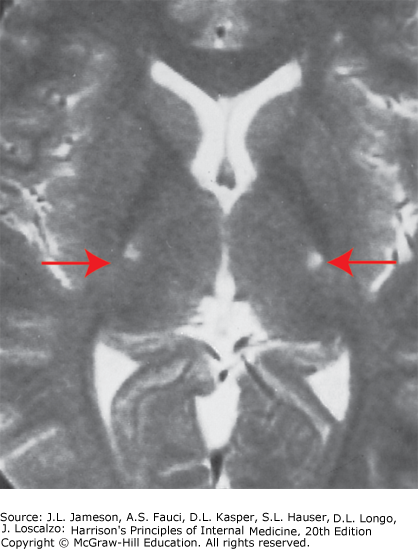

Amyotrophic lateral sclerosis: Axial T2-weighted magnetic resonance imaging (MRI) scan through the lateral ventricles of the brain reveals abnormal high signal intensity within the corticospinal tracts (arrows). This MRI feature represents an increase in water content in myelin tracts undergoing Wallerian degeneration secondary to cortical motor neuronal loss. This finding is commonly present in ALS, but can also be seen in AIDS-related encephalopathy, infarction, or other disease processes that produce corticospinal neuronal loss in a symmetric fashion.